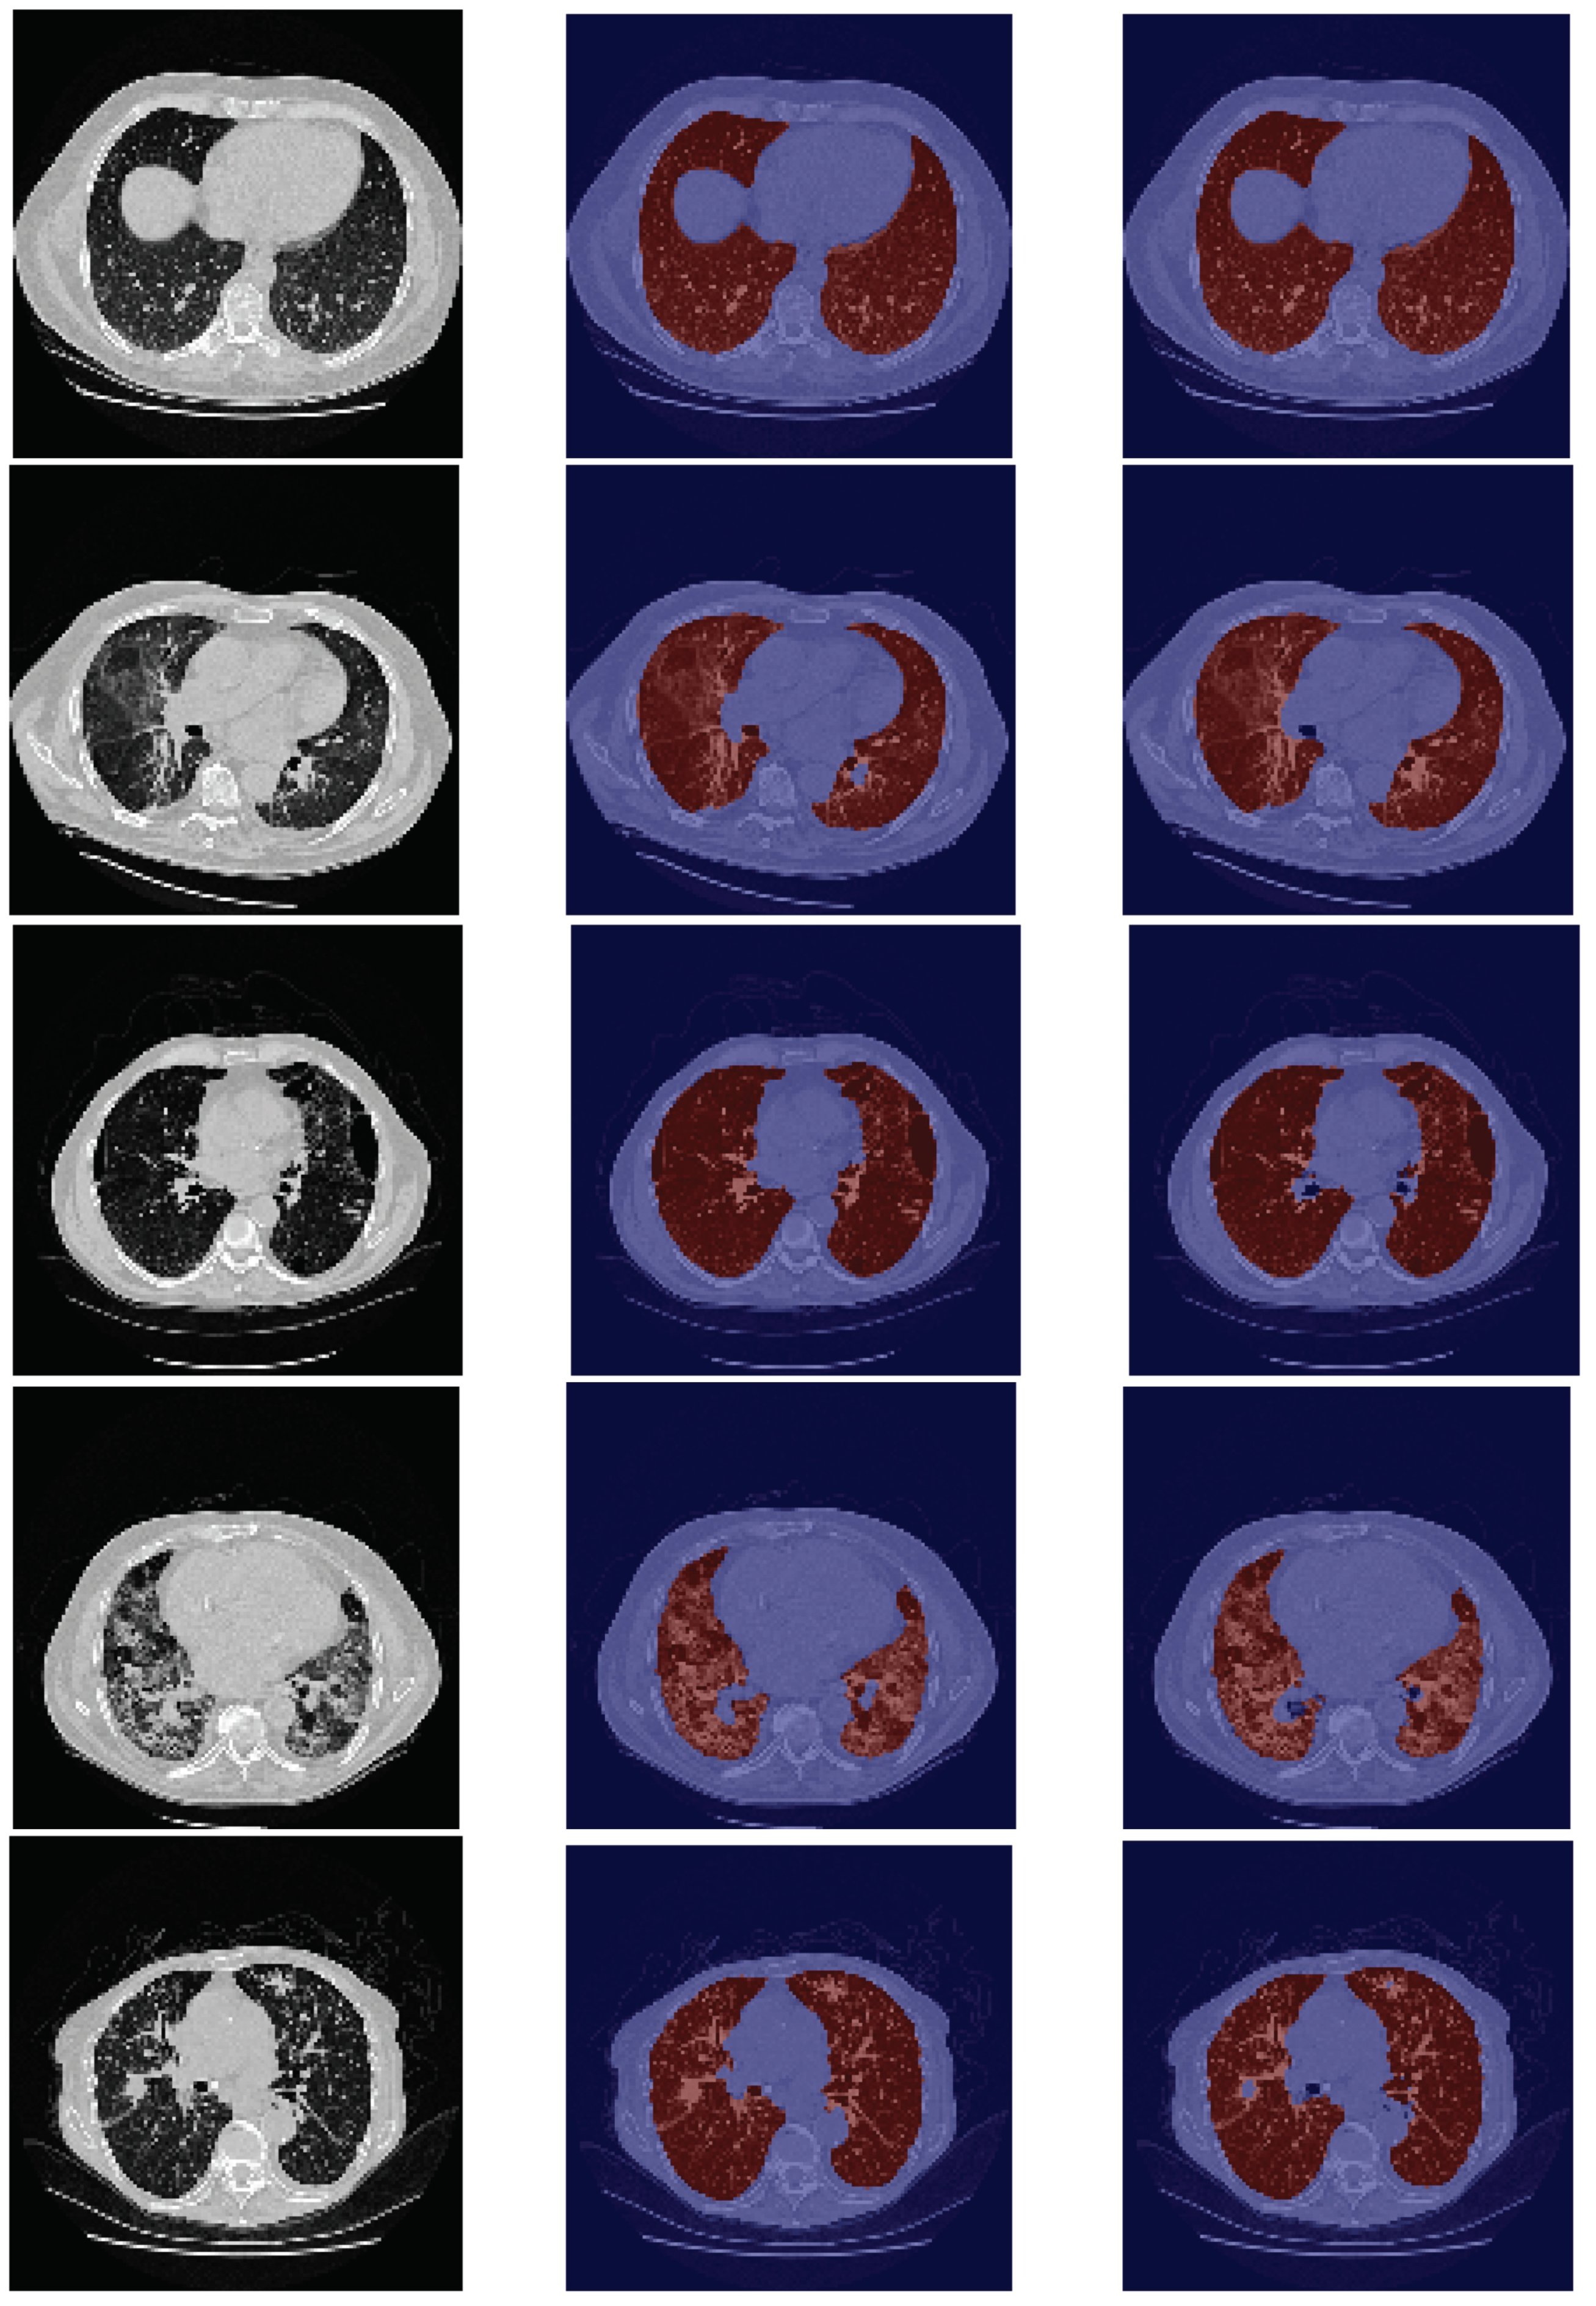

Concerning the VESSEL12 dataset, the model is able to produce good segmentation masks (see Figure 4), in general, for all ten scans, which were translated on a higher DSC, since this dataset does not contain intricate patterns. Moreover, the model does not erroneously classify other darker structures that are present in some slices as lungs.

Figure 4. Examples of VESSEL12 images for which the model produces good segmentation masks.

Another limitation comes from the annotations of the datasets. Those annotations come from different projects and followed different segmentation guidelines. There is no consensus on the inclusion/exclusion of some structures, such as airways or tumor masses. Examples of airways inclusion are shown in the second, third, fourth, and fifth rows in Figure 3 that belong to the HUG-ILD dataset, and examples of airways exclusion are shown in the last row in Figure 2, the first row in Figure 4, and the last row in Figure 5, that belong to the LCTSC, VESSEL12, and CHUSJ datasets, respectively. Examples of tumor masses inclusion are shown in last two rows in Figure 5 that belong to the CHUSJ dataset, and examples of exclusion are shown in the last row in Figure 2 that belong to the LCSTC dataset. Ideal, a very objective protocol of segmentation should be followed for the entire dataset annotation (training and test set) in order to not create label noise, which is responsible for overall quantitative performance degradation.